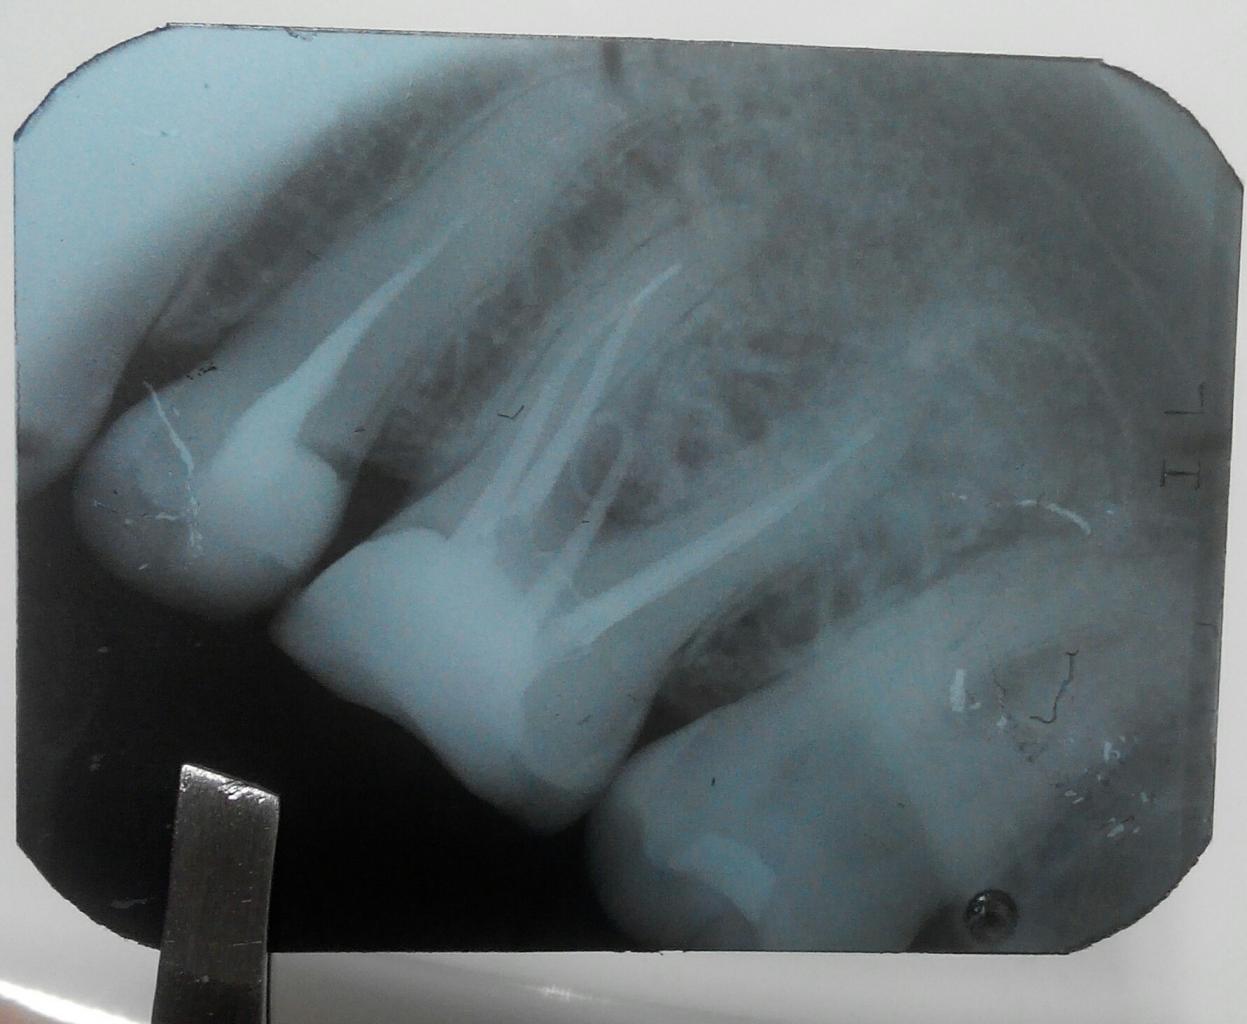

Нажмите на изображение для увеличения

Название: 20161228180642-1.jpg

Просмотров: 64

Размер:	96.0 Кб

ID:	11770364

Добрый вечер!)

Вот мой зуб, на который я вам жалуюсь давно, где свищ недавно появился.. Скрюченное на снимке это штифт гуттаперчивый всунули для проверки)

Канал фуркации? Интересно.

Угу, ятрогенный. Как и металлообтурация медиальной системы.

Ятрогенный или нет, видно на фото полости зуба. Инструмент, согласен, это клиническая неудача. К тому же он за изгибом, видимо.